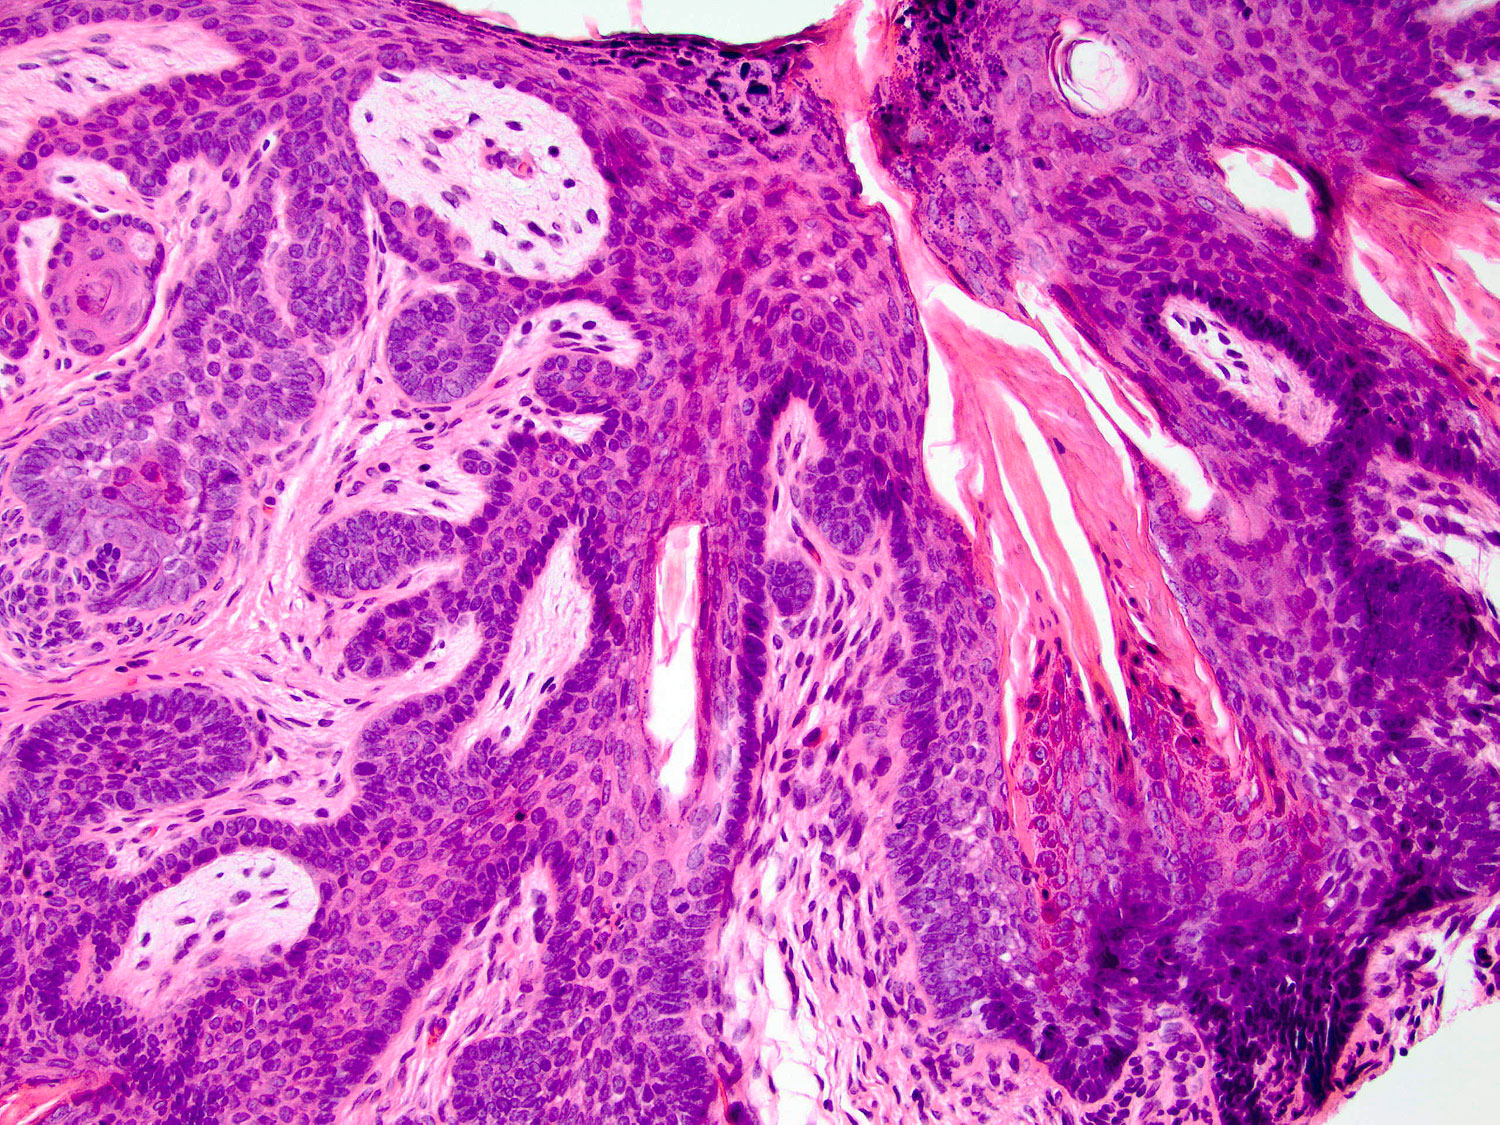

Secondary budding

H&E staining (20x objective)